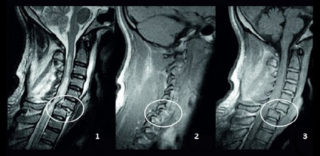

- компьютерная и магнитно-резонансная томография;

По результатам диагностики можно подтвердить факт смещения тел позвоночника и определить его степень:

- первая: позвонок на 25% отклонен от своего места локализации;

- вторая: тело смещено на 50%;

- третья: позвонок отклоняется на 75%;

- четвертая: тело смещено более чем на 75%.

Для постановки диагноза, необходимо пройти обследование:

- Рентген;

- Магнитно-резонансная или компьютерная томография.